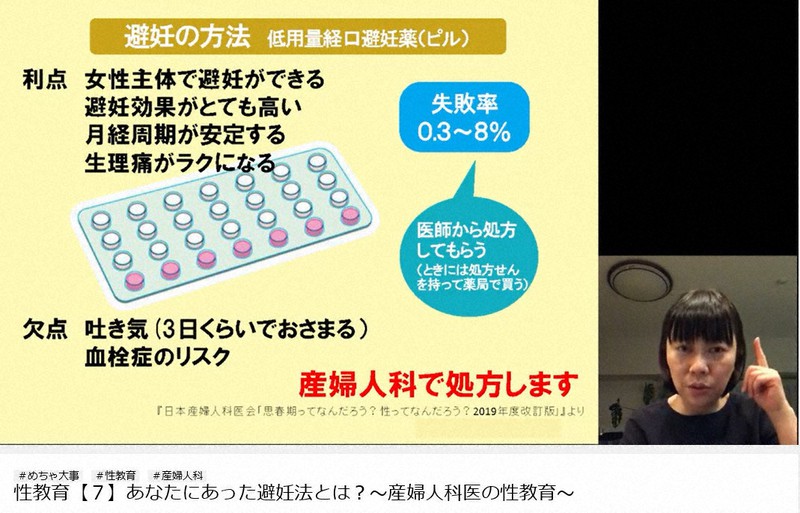

どのような処方避妊法が利用可能ですか?

処方箋による避妊薬は、医師または女性診療所を通じて入手できます。

その他の方法

経口避妊薬、ショット、パッチもホルモンレベルに影響します。有効率は 91 ~ 94 パーセントです。利用可能なブランドの例は次のとおりです。

- Alesse、Apri、Enpresse、Loestrin、Ortho-Novum、 Yasmin 、その他多数 (錠剤)